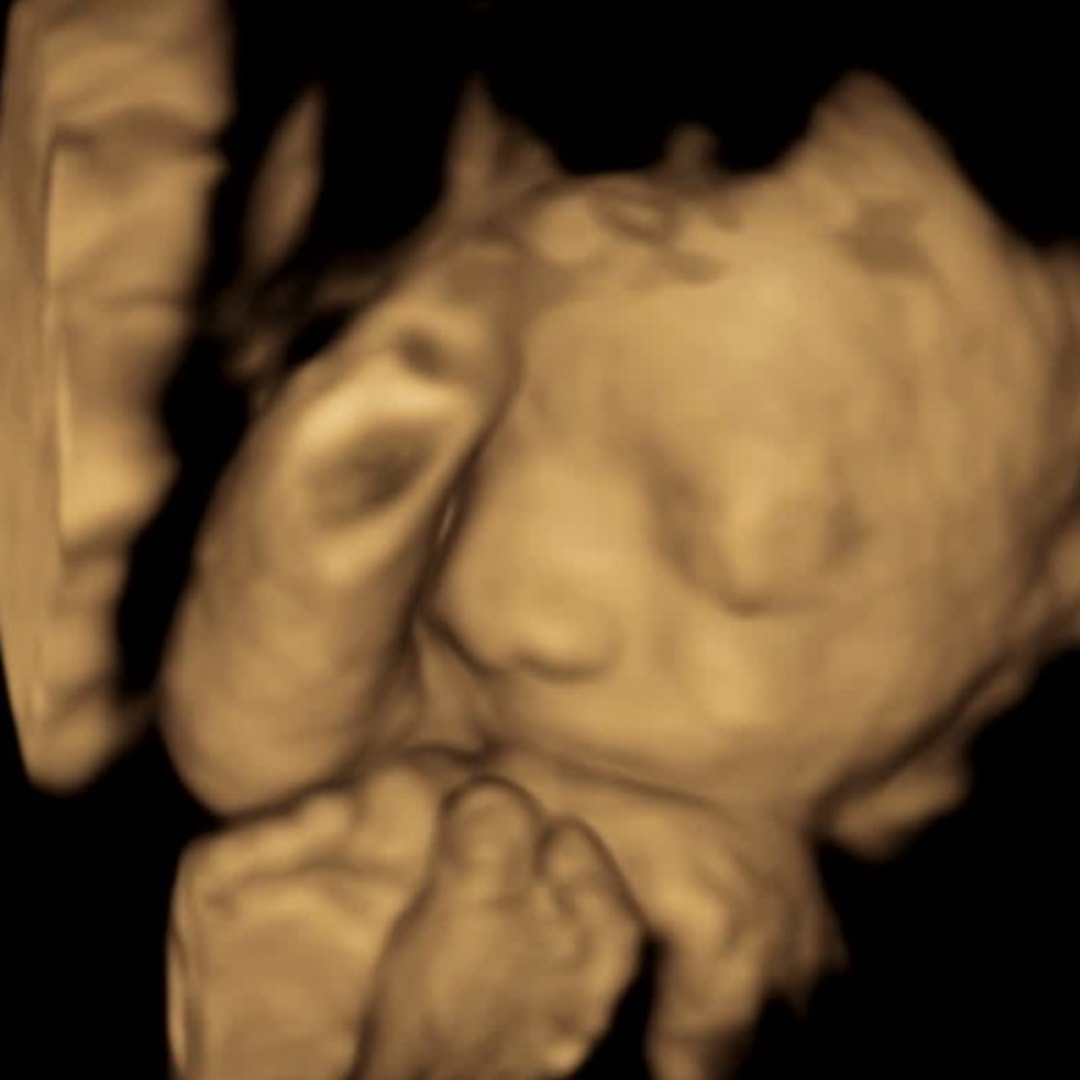

Tanya sanchez & Kevin Luna

Monrovia, CA

April 24, 2026